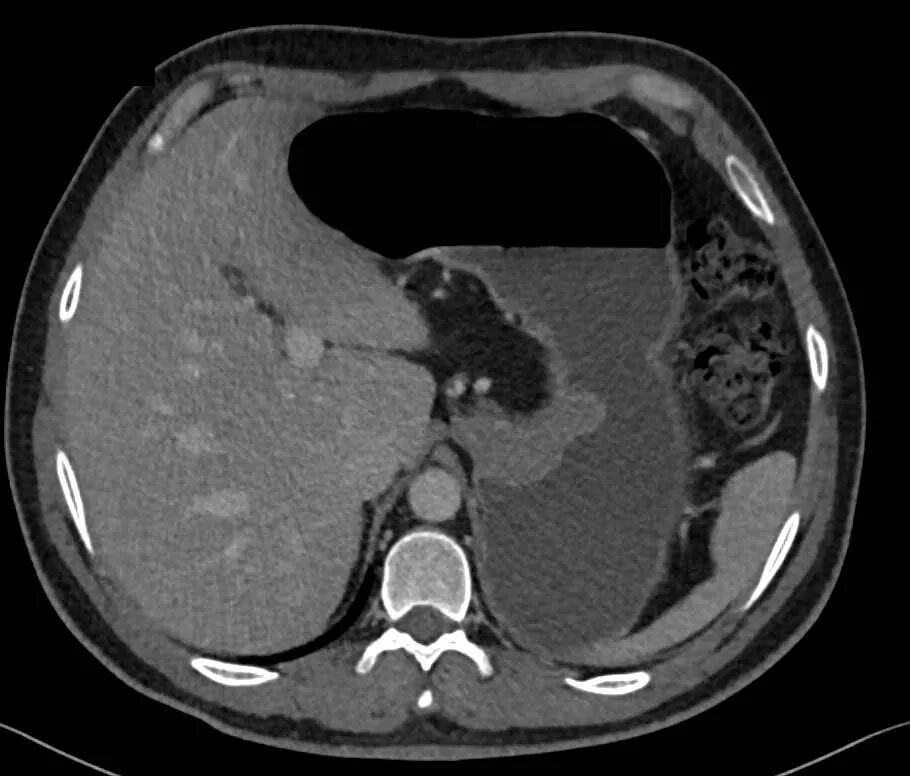

Язва желудка кт